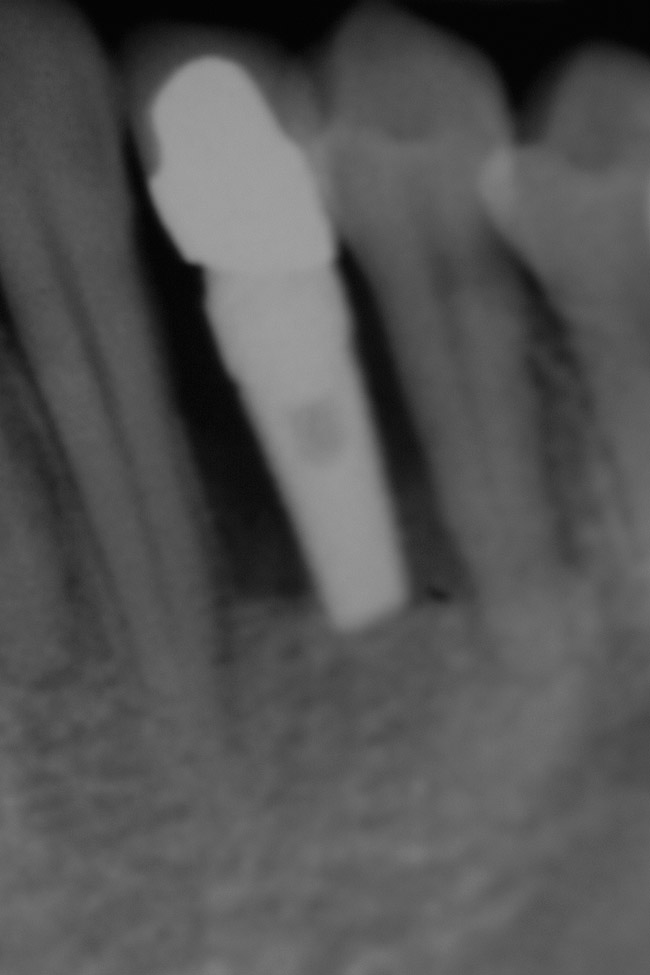

Figure 21  Radiograph of implant in position at the time of surgery of tooth No. 23.

Figure 21

Figure 23  Postoperative radiograph of zirconia abutment.

Figure 23

Following the first goal of orthodontia—moving tooth No. 22 to a proper functional and anatomical position—a periodontal reevaluation was performed, demonstrating an improvement in short- and long-term tooth prognosis. At this time, the decision was made to abort continual extrusion of teeth Nos. 21 and 22, although some attachment level discrepancy remained between Nos. 21 and 22 (Figure 14). Implant diagnostics ensued and included mounted study models and a diagnostic wax-up. A scanning appliance was created to demonstrate the desired prosthetic outcome requirements, and the patient was referred for computed tomography (CT) scans. CT scan assessment demonstrated successful orthodontically directed GBR to allow implant placement (Figure 15 through Figure 16). Only minor GBR therapy would be needed and could be accomplished simultaneously with implant installation. Guided implant placement occurred, using an open flap approach (Figure 17). During surgery, root dehiscences were noted on teeth Nos. 21, 22, 24, and 25, as well as the anticipated dehiscence following implant placement at No. 23 (Figure 18). A positioning reference (index) was secured after implant placement to facilitate a provisional prosthesis at stage II surgery. Cortical perforations then were placed adjacent to the implant to encourage angiogenesis (Figure 18), and mineralized freeze-dried bone allograft enhanced with platelet-derived growth factor was placed over the dehiscences for purposes of guided tissue regeneration and GBR (Figure 19). A highly resorbable collagen membrane was placed to stabilize the allograft. The flap was coronally repositioned, and primary-intention wound healing was achieved (Figure 20 and Figure 21). Following 4 months of stage I surgery, implant uncovery and immediate provisionalization were performed in conjunction with connective tissue grafting. Final orthodontic tooth movement then ensued, using the implant as anchorage to optimize end-tooth movements, interroot separation, and the cuspid-protected occlusal scheme. A final impression then was secured, and a zirconia abutment (Figure 22) with an all-ceramic restoration was fabricated for the prosthetic phase completion of No. 23 (Figure 23 through Figure 25).